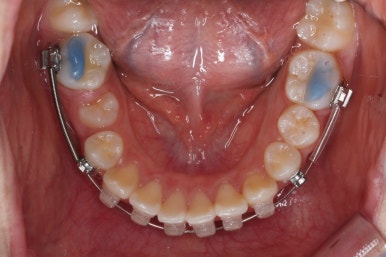

부산치아교정잘하는곳 처음 오셨을 때의 입안 모습입니다.

맨 우측 밑에 사진을 보시면 이가 하나 더 나와야 할 자리에(화살표) 앞뒤로 치아가 쓰러지면서 자리를 거의 없애버렸습니다.

따라서 이가 나올래야 나올 수가 없는 상태였습니다.

왼쪽 맨 위 사진을 보시면 아래 치열의 중앙이 한 쪽으로 쏠린 것을 알 수 있는데요. 역시 치아가 나올 자리가 없어지면서 치열이 쏠러버렸다는 것을 알 수 있습니다.

아래쪽이 더 시급하므로 브라켓 부착을 하여 가지런히 하기 시작했고 위쪽은 악궁확장장치를 입천장에 하여 위턱뼈를 가로로 넓혀주기 시작합니다.